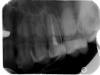

olga.t Опубликовано 25 декабря, 2012 Поделиться Опубликовано 25 декабря, 2012 (изменено) Добрый день! Дня 4 назад над давно депульпированным зубом (пятерка сверху) образовался свищ. Страховая записала к стоматологу только на сегодня, до этого рекомендовали полоскать рот раствором хлоргексидина. С хлоргексидином содержимое из свища перестало выделяться, но сам он не закрылся. Свищ чувствуется, сам зуб не беспокоит. Сегодня стоматолог сделал рентген, промывать нигде ничего вообще не стал, сказал - not urgent. Вердикт - перелечивать канал (ы? их там сколько?). Вопрос - это обязательно? Что-то я в успехе этого предприятия не уверена, боюсь остаться вообще без зуба. Дело происходит сильно не в России, возможность коммуникации с врачом ограничена, в России буду не скоро. Чем были запломбированы каналы - без понятия. И еще вопрос: как долго можно полоскать все это хозяйство хлоргексидином или может еще чего-нибудь поприкладывать? Хочу к другому доктору еще сходить. Спасибо. Изменено 25 декабря, 2012 пользователем olga.t Ссылка на комментарий

zybnaya feya Опубликовано 25 декабря, 2012 Поделиться Опубликовано 25 декабря, 2012 Вам гуттаперчевый шрифт как указатель показывает источник проблемы. Находится он как раж в области верхушки корня зуба. Что вы собрались полоскать,если инфекция внутри канала? То что в кости и свищ-это следствие. Решайте проблему " на корню", как говорится))) перелечивайте иначе потеря зуба неизбежна Ссылка на комментарий